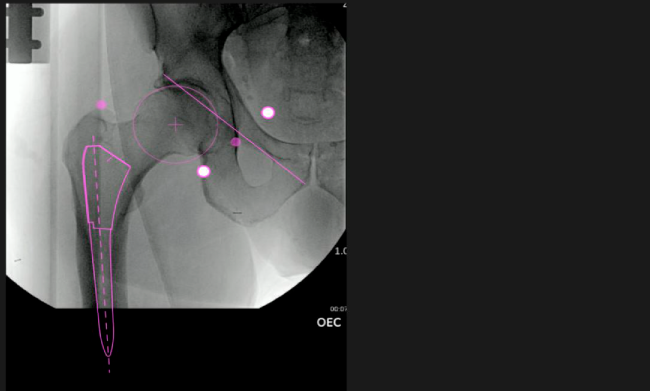

Planeación preoperatoria mediante la creación de plantillas digitales para reemplazo de cadera y análisis intraoperatorio

Desplazamiento y offset para posicionamiento óptimo del componente (vástago) femoral.

Verificación de la posición deseada del implante que potencialmente puede ayudar a reducir la probabilidad de dislocación protésica y aumentar la estabilidad de la articulación.